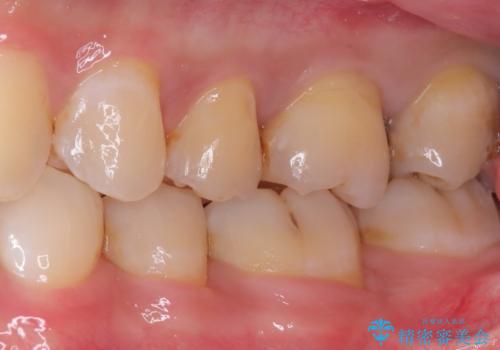

初診でいらした患者様で、口腔内を確認したところ左上6番目と7番目の歯の接する面を中心に両方の歯に虫歯が認められたため、セラミックインレーでの修復治療となりました。

左上6番の歯には元々修復物が入っていましたが、それも一度除去し新たにMOD窩洞のセラミックインレーをセットしました。